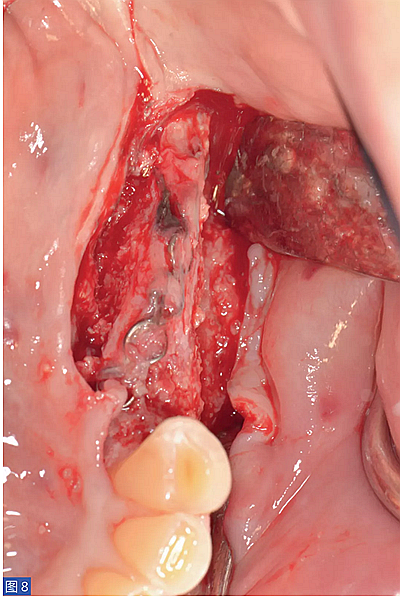

圖9:病例1. 術(shù)后6 個月,再生組織區(qū)域2 顆種植體。